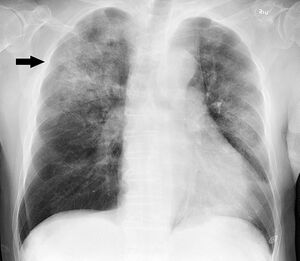

Chest X-ray of a case of Haemophilus influenzae, presumably as a secondary infection from influenza. It shows patchy consolidations, mainly in the right upper lobe (arrow).